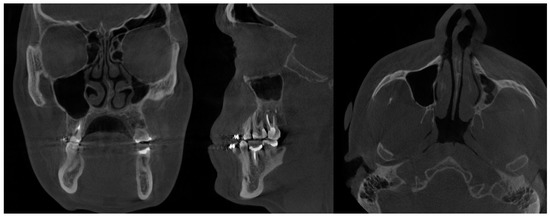

- (2)

- Type 2 in-pure SSS (iSSS) (Figure 3, Figure 4 and Figure 6) related to maxillary deformation (might be related to maxilla-mandibular skeletal class II/III deformities or others), clinically asymptomatic, not related to trauma or surgery, 1–3 MS walls retracted, OMC clear, no opacification, like suggested by Lee et al., the “not so silent sinus” [18];